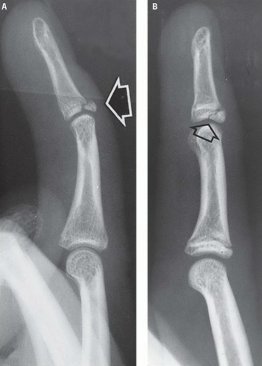

What type of fracture is this?

Chip

What is a chip fracture?

Isolated bone fragment NOT caused by tendon or ligament